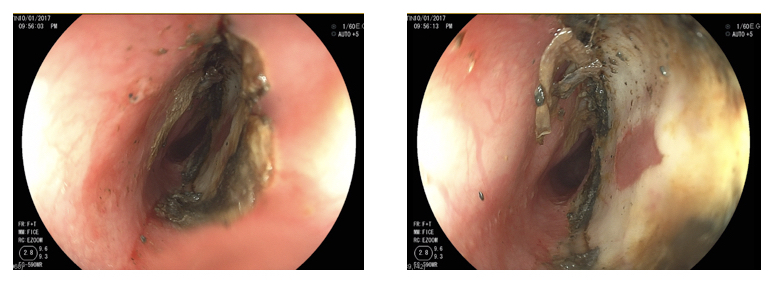

Inmediatamente llegamos, miraron los RX y dijeron que no daba espera, en el momento no había endoscopista pediátrico por lo que un endoscopista para adulto a quien hoy digo que fue un mago, luego de 4 largas horas pudo lograr sacarle la batería que ya había causado una quemadura del 80% de su esófago del tamaño de un pitillo. En ese momento una angustia me mataba porque jamás debí permitir tener tantas cosas «NO APTAS PARA SU EDAD» a su alcance.

Las secuelas según los médicos serían de por vida, podría quedar con una estenosis lo que acarreaba terapias o alguna cirugía para cortar la parte afectada o en su defecto terapias para que volviera a funcionar normalmente su esófago. También implicaba un atraso gravísimo en su alimentación, de hecho demoró un mes exacto sin tomar agua ni consumir ningún tipo de alimentos (Lo hacían por NPT, lo que lo sometió a un cateterismo central a tan corta edad), problemas para hablar, problemas digestivos, respiratorios y sin contar el trauma con el que quedó con solo ver una bata o estar en un hospital. (Exámenes de sangre, la postura del catéter, médicos especialistas lo visitaban 3 veces al día, enfermeras aplicándole morfina y esteroides para evitar una infección o una perforación que era fatal para su vida).